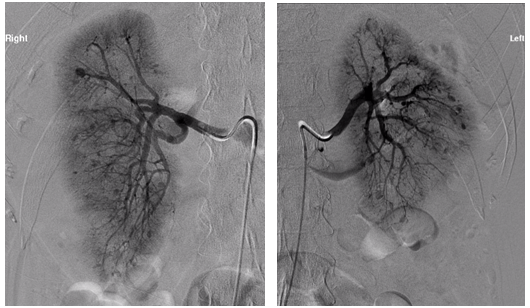

An unclear picture led to a CT pulmonary angiogram, which did not reveala pulmonary embolism but it was incidentally found that there were bilateral large renal haematomas (Figure 1). Subsequent blood tests revealed worsening renal function, inflammatory markers, and anaemia requiring blood transfusions. The patient was also found to be ANCA positive with a raised MPO titre of 134U/ml. A renal angiogram was performed and showed several renal artery aneurysms (Figure 2).

Figure 2 Renal angiogram right and left showing extensive renal artery aneurysms, with compression of left renal artery as a result of the haematoma.